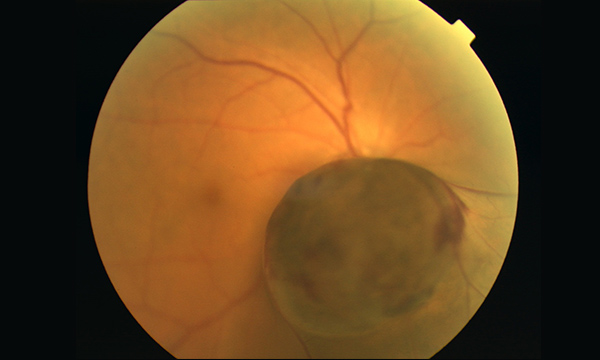

眼底検査で脈絡膜に黒色の腫瘍があり、高さが3mm以上、増大傾向がある場合、悪性黒色腫の可能性が高いです。診断のために、I-SPECT検査や眼内液の腫瘍マーカー測定を行い、通常生検は行いません。治療は、腫瘍の大きさ、位置、転移の状態によって、眼球摘出、サイバーナイフを用いた放射線療法、全身化学療法などを行います。